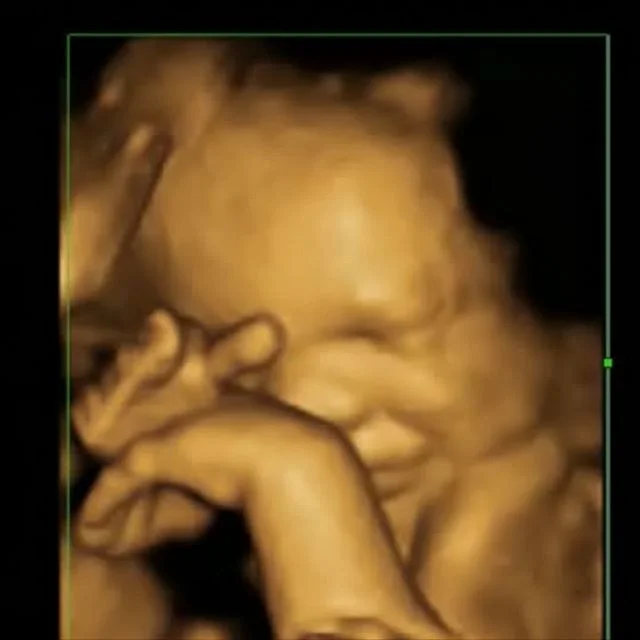

• 3D Obstetric ultrasound

Ultrasound is performed in the rooms and in conjunction with Wellington Ultrasound. A scan can give us a lot of information and allows individualisation of pregnancy management and provide reassurance.